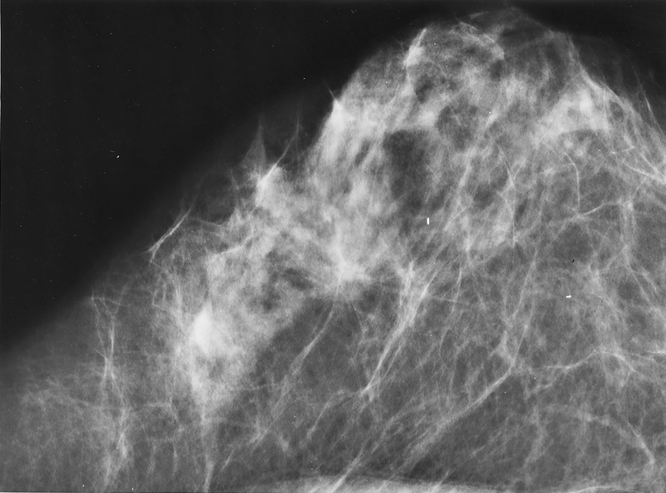

Patients were divided into four groups based on mammographic presentation: mass (Fig. 1), calcification (Fig. 2), mass with calcification (Fig. 3), and architectural distortion (Fig. 4). Pathologic findings were correlated with mammographic presentation. The data were analyzed using the SPSS statistical program (SPSS Inc., Chicago, IL). The significance of differences in categorical variables was evaluated using the chi-square test. The significance of differences in continuous variables was evaluated using one-way analysis of variance followed by t tests if the one-way analysis was significant.

Figure 2. Malignant breast tumor presenting as calcifications on mammogram.